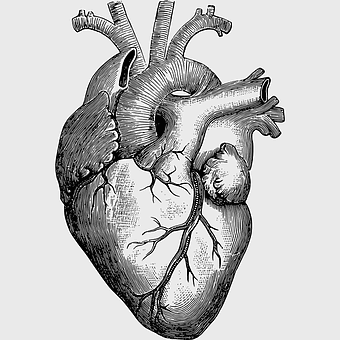

human heart diagram, monochrome anatomy drawing, black and white heart illustration, human organ sketch, cardiovascular system diagram, medical illustration heart, heart structure outline -

human heart anatomy, cardiac muscle illustration, circulatory system model, heart health visual, cardiovascular organ diagram, medical heart image, visceral structure depiction -